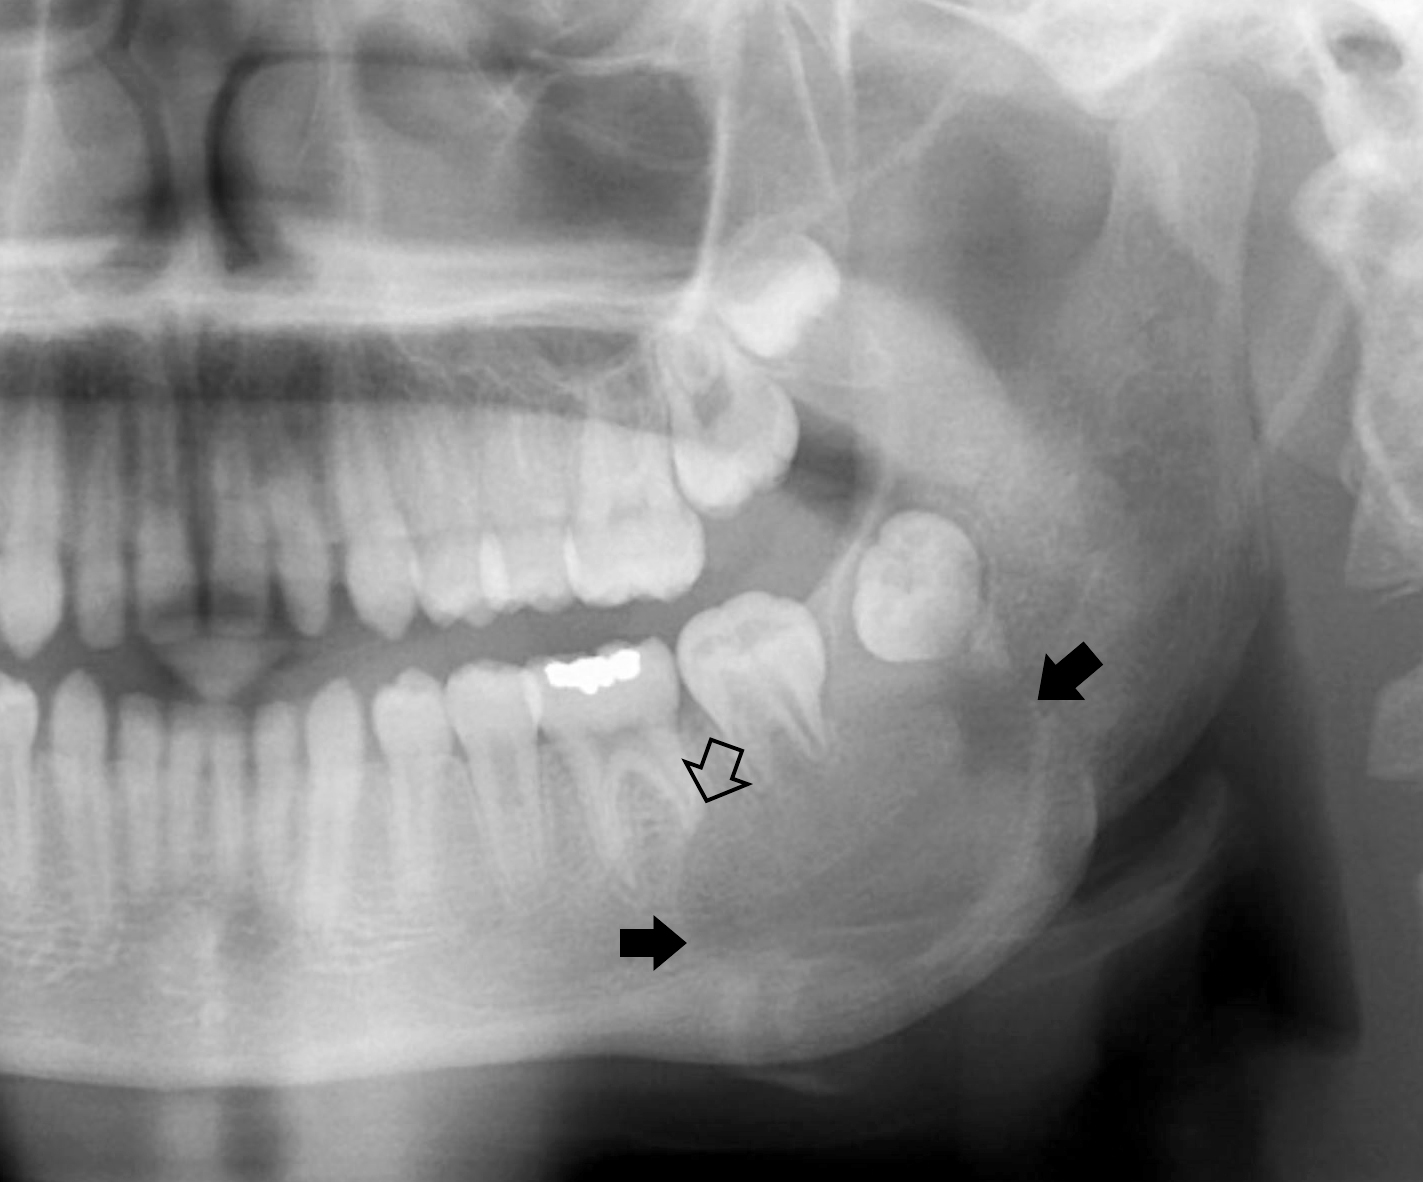

Radiology description

- Ameloblastoma, conventional

- Expansile multilocular radiolucency, well defined, corticated border

- Some cases exhibit classic soap bubble appearance

- May or may not be associated with impacted tooth / teeth

- Resorption or displacement of tooth roots

- Reactive bone formation may occur, most commonly in desmoplastic ameloblastoma, which may resemble a fibro-osseous lesion radiographically due to the presence of osteoplasia

- May have a unicystic radiographic appearance on plain images; requires microscopic examination for distinction from ameloblastoma, unicystic type (Dentomaxillofac Radiol 2018;47:20170288)

- Ameloblastoma, unicystic type

- Unilocular radiolucency, well defined, corticated border

- Often associated with an impacted tooth, specifically mandibular third molar

- Root resorption may occur

- Cortical perforation in 33% of cases

Radiology images